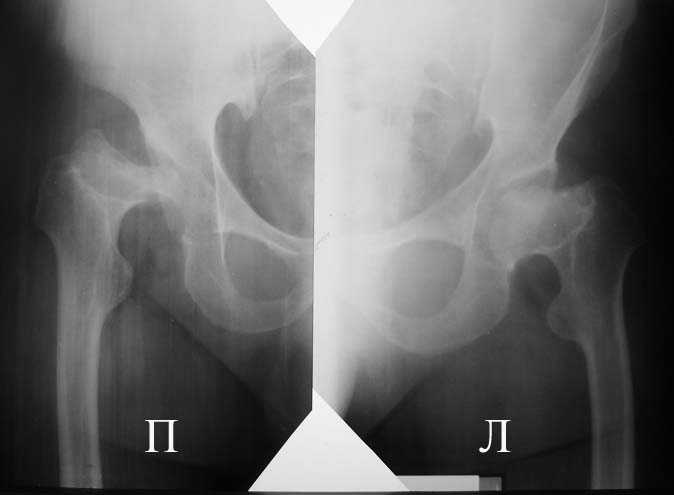

Прямая проекция т/б суставов